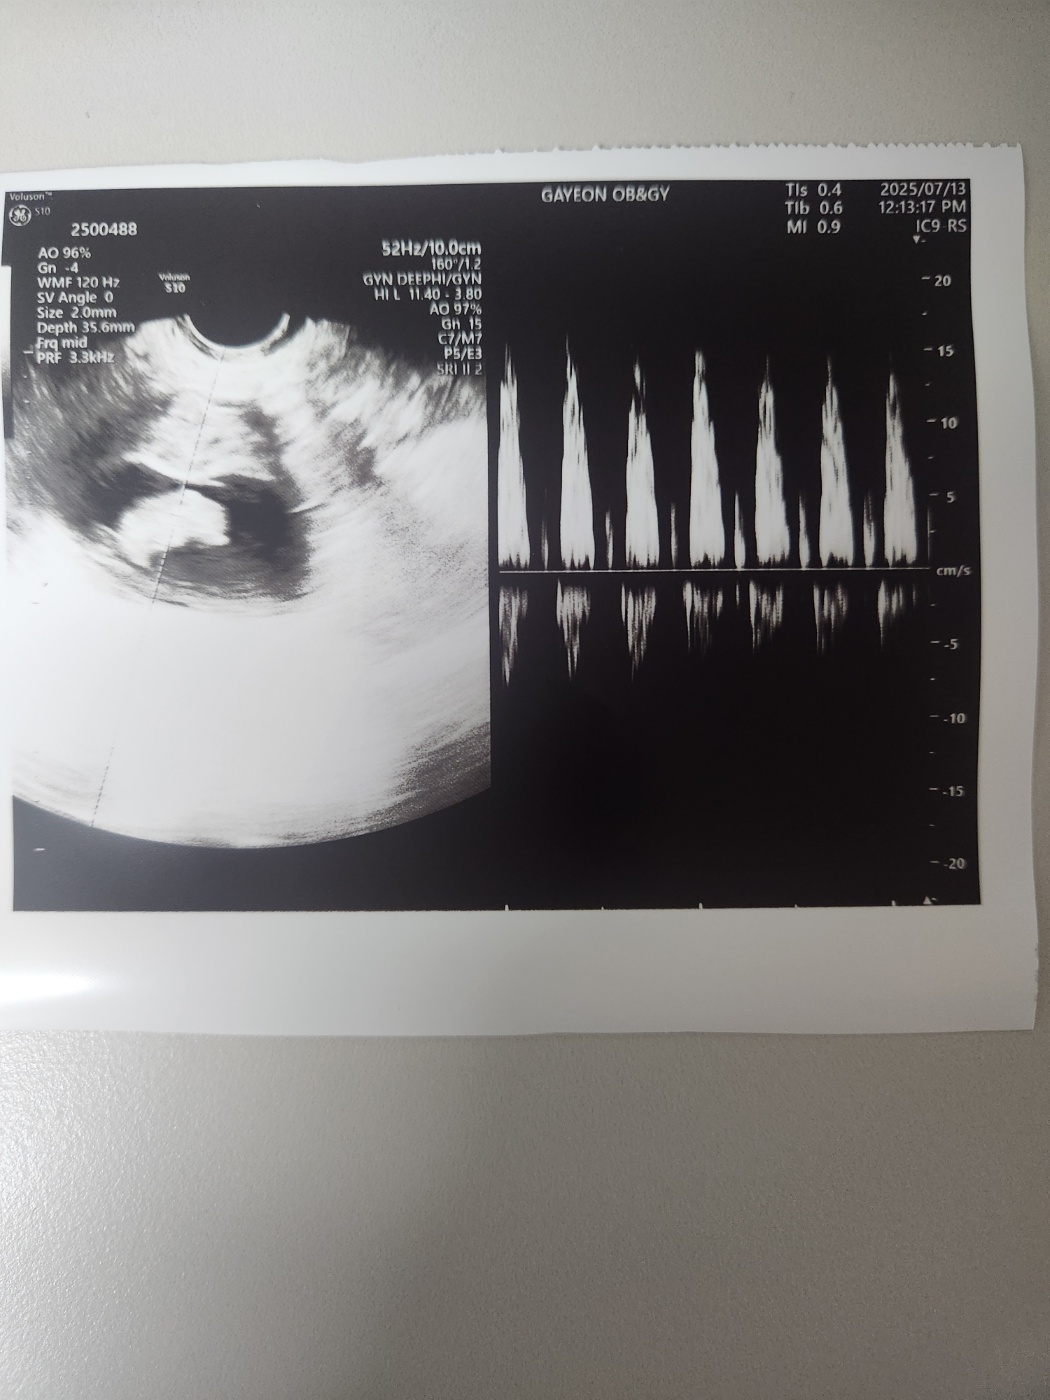

임신 9주 차의 아기 심장소리는 더욱 잘 들렸고 힘차게 뛰고 있었습니다.

의사 선생님께서는 건강하게 주수에 맞게 아주 잘 크고 있다고 말씀해 주셨습니다.